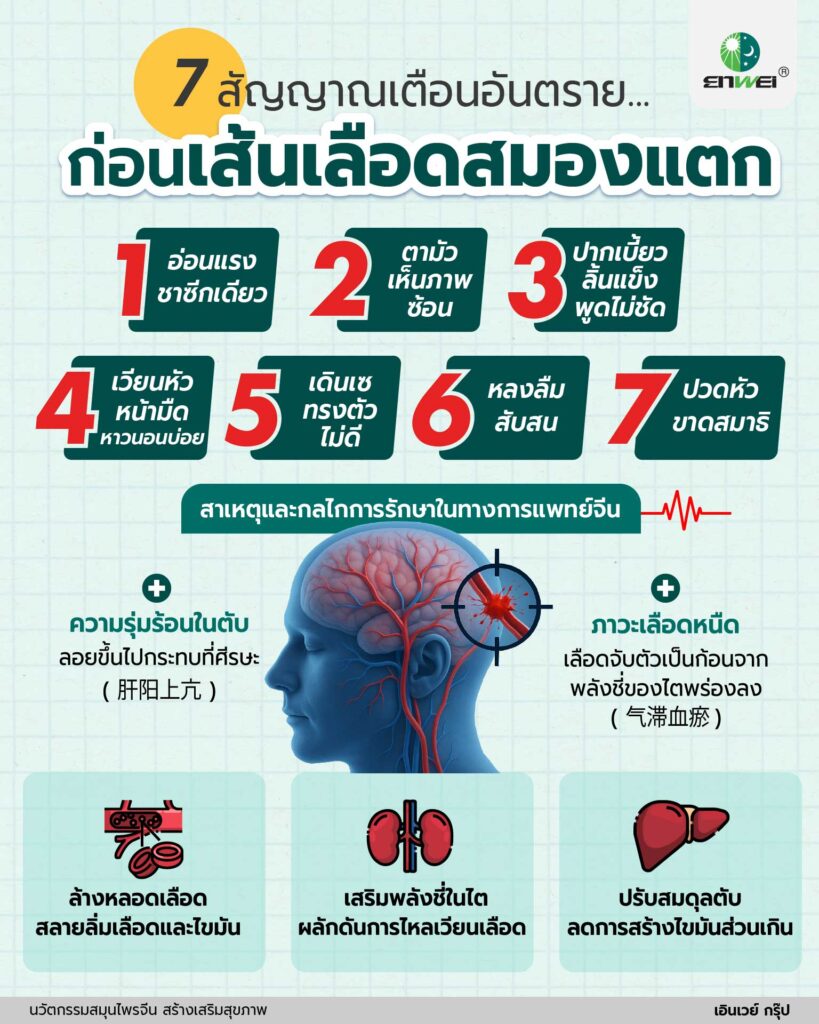

BEFAST สัญญาณเตือนโรคหลอดเลือดสมอง

- B – Balance เวียนศีรษะ เดินเซ ทรงตัวไม่ได้

- E – Eyes ตามัว มองไม่ชัด เห็นภาพซ้อน

- F – Face หน้าเบี้ยว ยิ้มแล้วมุมปากสองข้างไม่เท่ากัน

- A – Arm แขนขาอ่อนแรง ยกไม่ได้

- S – Speech ลิ้นแข็ง พูดไม่ชัด พูดติดขัด

- T – Time หากพบอาการข้อใดข้อหนึ่ง ให้รีบไปโรงพยาบาลทันที

การรักษาโรคหลอดเลือดสมองในทางการแพทย์จีน

โรคหลอดเลือดสมองเกิดจาก ภาวะหยาง (ความร้อน) ในตับมีมากเกินไป จนลอยตัวขึ้นไปกระทบที่ศีรษะ ร่วมกับภาวะเลือดมีความหนืดมากเกินไปจากพลังชี่ของไตพร่องลง การแพทย์จีนจึงเน้นการรักษาแบบองค์รวมเพื่อปรับสมดุลร่างกาย ด้วยตำรับยาสมุนไพรจีนในรูปแบบสารสกัดเข้มข้น ซึ่งประกอบด้วย Huangqi, Chishao, Danshen, Dilong, Chuanxiong, Quanxie ฯลฯ ผ่านการสกัดที่ทันสมัย ควบคุมปริมาณสารออกฤทธิ์ได้อย่างคงที่และแม่นยำ และผ่านการศึกษาวิจัยทดลองทางคลินิกตามหลักการแพทย์สากล ซึ่งมีกลไกการออกฤทธิ์ดังนี้

- สลายภาวะเลือดคั่งและลิ่มเลือด

- ลดความหนืดของเลือด ลดการเกิดลิ่มเลือด

- ลดไขมันในเลือด คอเลสเตอรอล ไตรกลีเซอไรด์ LDL และเพิ่ม HDL

- ลดการอักเสบของผนังหลอดเลือด

- เพิ่มความยืดหยุ่นและลดการปริแตกของผนังหลอดเลือด

- เพิ่มการไหลเวียนเลือด เพื่อให้เลือดไปเลี้ยงส่วนต่าง ๆ ของร่างกายได้ดี